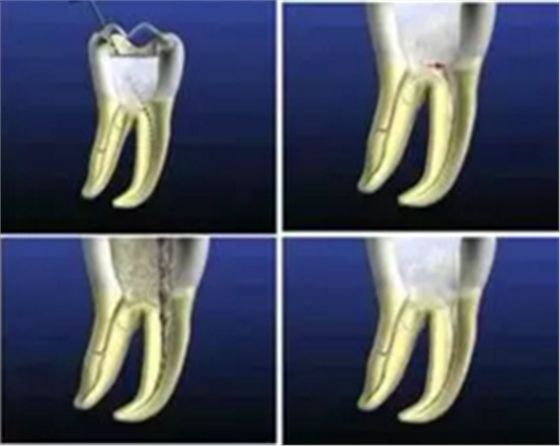

一、根管充填的步驟

1. 主牙膠尖的確認(rèn)

由于器械磨損或生產(chǎn)誤差影響,主牙膠尖與實際型號可能存在一定偏差,需要進(jìn)行測量確認(rèn)。

( 1 )通過帶有孔徑的量尺選擇主牙膠尖。

器械的選擇:選擇器械作為中銼,插入量尺孔中。器械正好插入小孔,下面剛剛能夠觸到,該小孔為器械合適直徑的小孔。

牙膠尖的選擇:選用稍微細(xì)點的牙膠尖插入,孔背面切平,獲得的牙膠尖端直徑和中銼直徑一致。

( 2 )牙膠直徑合適后確認(rèn)長度,獲得主牙膠,然后選擇主牙膠尖。

主牙膠尖插不進(jìn)去表明主牙膠尖有些粗;插到外面去表明主牙膠尖有些細(xì)。通過反復(fù)篩選,選擇剛好可以卡在里面的牙膠尖,完成主牙膠尖的確認(rèn)。

圖為 ISO 標(biāo)準(zhǔn) 20 號牙膠尖,黃顏色。圖中從左向右依次為 02 、 04 、 06 錐度。

圖為 ISO 標(biāo)準(zhǔn) 25 號牙膠尖,紅顏色,尖端直徑為 0.25mm 。圖中從左向右依次為 02 、 04 、 06 錐度。

圖為 ISO 標(biāo)準(zhǔn) 30號牙膠尖,藍(lán)顏色。圖中從左向右依次為 02 、04 、06 錐度。

2. 糊劑的導(dǎo)入

選好牙膠尖后開始根管充填,側(cè)方加壓術(shù)中可使用螺旋充填器導(dǎo)入糊劑。不要把螺旋充填器一直放在根尖狹窄部位置,避免糊劑超填,造成治療失敗。

螺旋充填器正確的使用步驟:螺旋充填器固定在距根尖孔 4-5mm 位置,進(jìn)行旋轉(zhuǎn)輸送。然后用牙膠尖或光環(huán) C 針做全長輕輕提拉,再使用螺旋充填器進(jìn)行輸送,保證根尖下端的填充。

3. 主牙膠尖的插入

主牙膠尖應(yīng)提拉插入,以避免超填。

主牙膠尖常選擇 02 錐度主牙膠尖,有下面幾個優(yōu)點:

( 1 )能夠很好地到達(dá)根尖狹窄部。

( 2 )側(cè)方加壓時有較大空間,封閉型好。

4. 輔牙膠尖的插入

主牙膠尖插后選擇側(cè)方加壓器進(jìn)行側(cè)方加壓根管充填。

( 1 )側(cè)方加壓器的選擇:

術(shù)前應(yīng)選擇好,直徑為到達(dá)距根尖狹窄部2 -3mm 位置,避免將主牙膠尖擠壓出根尖狹窄部。

( 2 )操作:加壓時沖牙膠位置擠壓,拿出側(cè)方加壓器后立即插入輔牙膠尖。

金屬器械取出時牙膠尖有回彈,如果輔牙膠尖放置時間過長,不能到達(dá)側(cè)方加壓位置,可能造成中間空隙??稍谘滥z尖上蘸一些糊劑送入。關(guān)鍵是迅速插入輔牙膠尖。

5. 致密加壓

插入輔牙膠尖后,去除多余牙膠,使用垂直加壓器垂直致密加壓。

操作:進(jìn)行完根管充填、牙膠放好后,使用垂直加壓器,從根管口向根管方向垂直加壓,壓入 1-2mm 。

優(yōu)點 :封閉冠,預(yù)防牙冠方的的細(xì)菌感染。

6. 術(shù)后 X 線片

術(shù)后 X 線片用來評定根管充填 長度、致密度(管壁清晰、側(cè)枝)等指標(biāo)。

圖為根管充填術(shù)后 X 線片。圖中可見,根管充填較好。右下圖有白色小點,為側(cè)方加壓導(dǎo)致糊劑擠出所致,表明根管充填比較致密。

致密、恰到好處的充填可去除干凈根管里感染灶,機體逐漸恢復(fù)。

多根牙時候需進(jìn)行偏移投照,正位投照無法說明具體哪根牙根管充填效果。